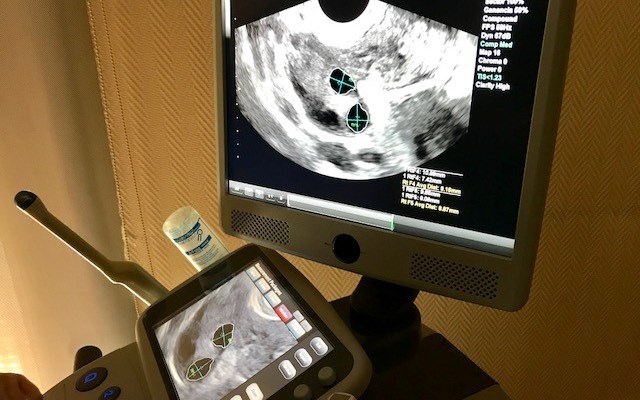

Tecnología

8 de enero de 2018

Mayor precisión en el proceso de la reproducción asistida

Un nuevo ecógrafo mejora la exactitud del diagnóstico y evolución de todo el tratamiento

En los procesos de reproducción asistida la técnica de diagnóstico por imagen es vital, ya que se emplea la ecografía vaginal para obtener toda la información necesaria sobre el estado inicial de la paciente, tanto en relación a su reserva ...